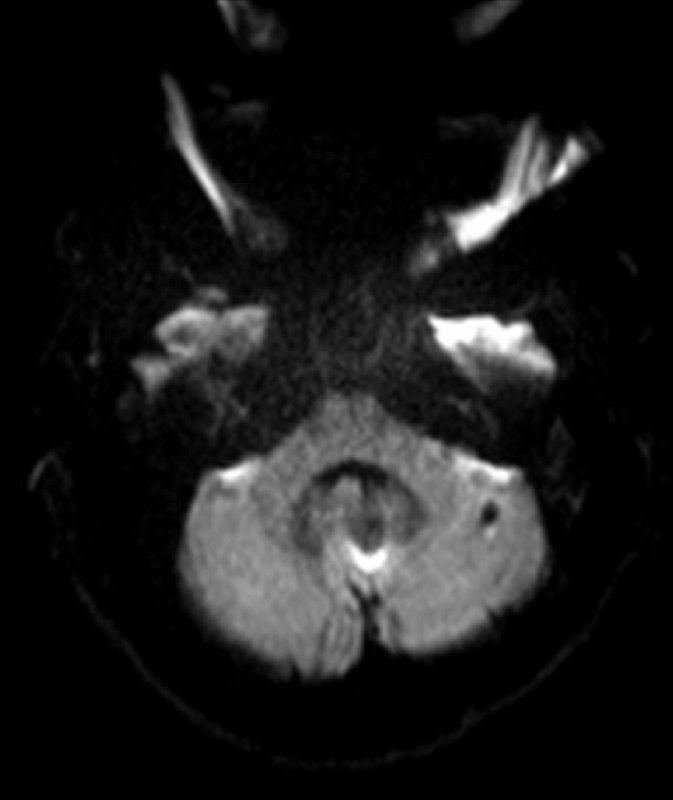

Пациент 35 лет. Жалобы на онемение правой руки. Других жалоб нет.

Характер травмы:

Упал с велосипеда головой вниз.